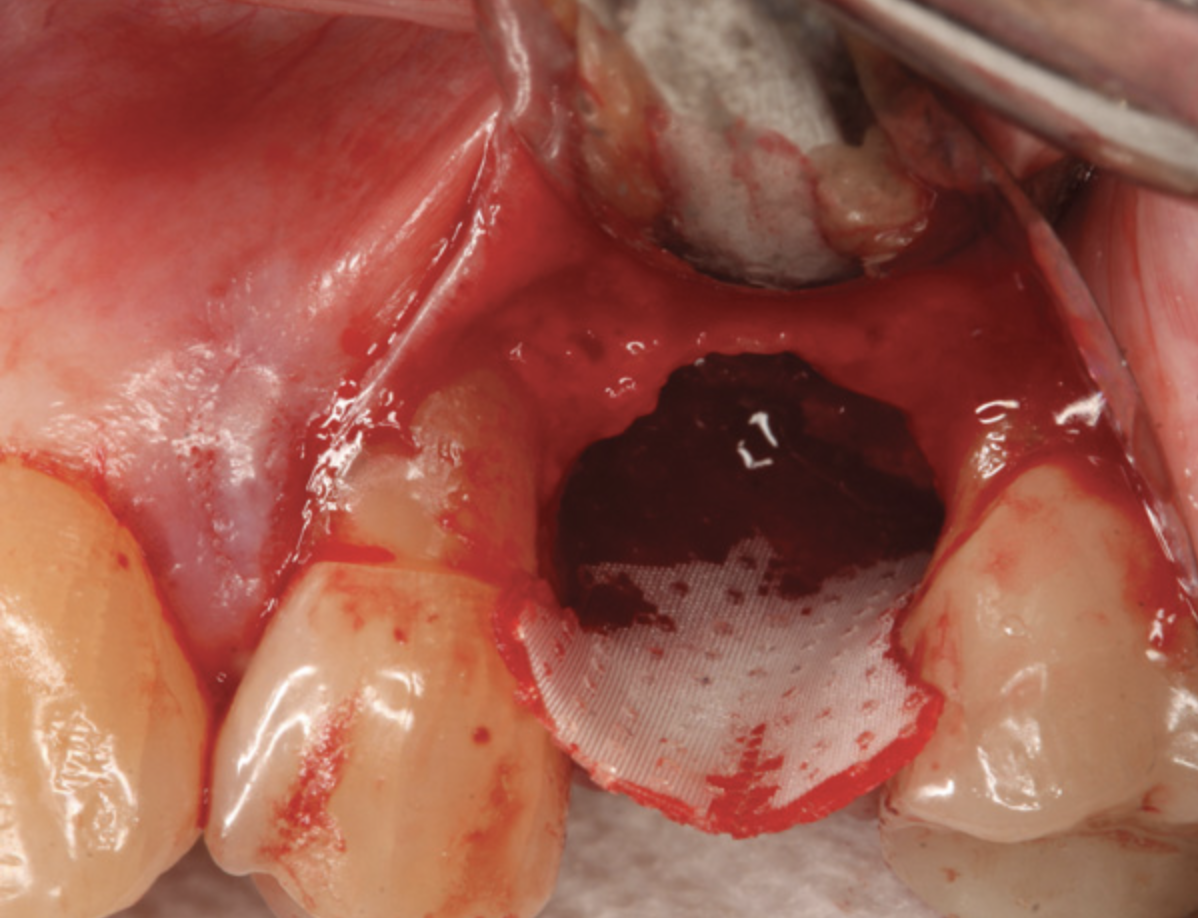

In a case presented in Figure 9 through Figure 11, the synthetic barrier was inserted at the time of removal of a tooth with significant bone loss on the palatal aspect (Figure 9). The rigidity of the material not only enabled containment of the bone replacement graft material, but also the initial formation of the site in the desired alveolar ridge shape (Figure 10). Six weeks later, there was no evidence of inflammation and the area was healing quite well (Figure 11). Not only was the alveolar ridge back to its ideal shape at the crest, but there was also a widened zone of keratinized tissue where primary closure was not attempted over the barrier.

Fig 9. A semi-rigid synthetic barrier was inserted in a subperiosteal manner where a significant loss of palatal bone and thin buccal plate existed.

Figure 9